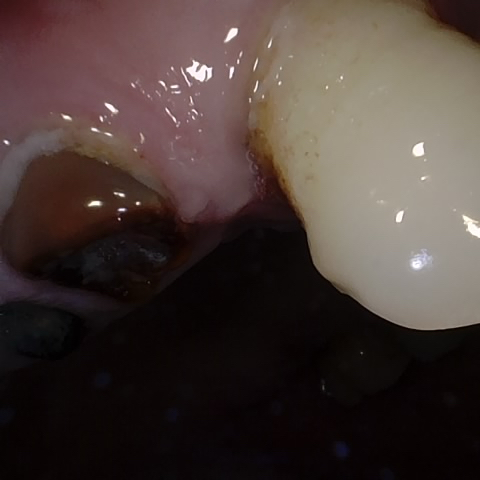

Annotated as "Good"